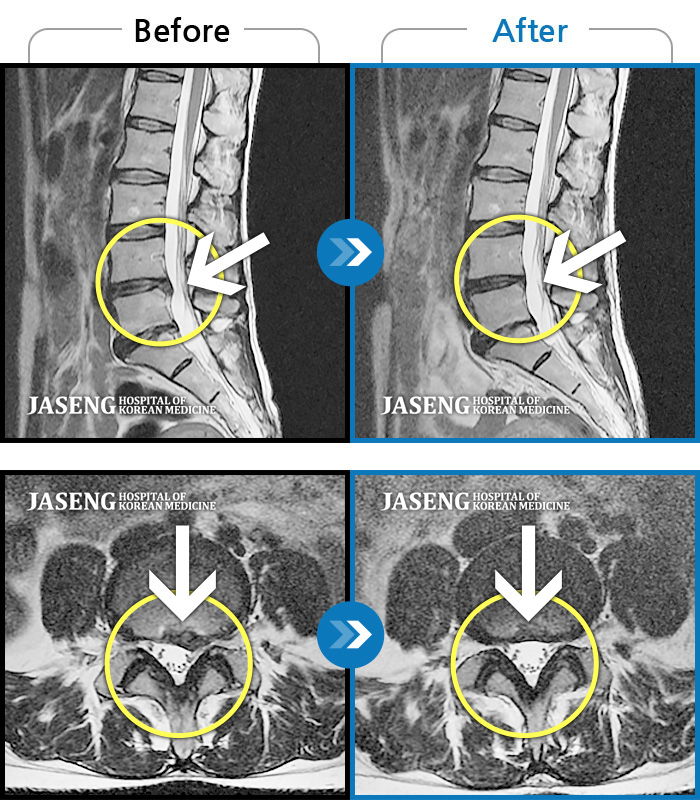

MRI 치료사례

허리디스크가 흘러내려온 상태로 허리, 골반, 다리가 아파 잠을 못 잘 정도로 통증이 심했습니다.